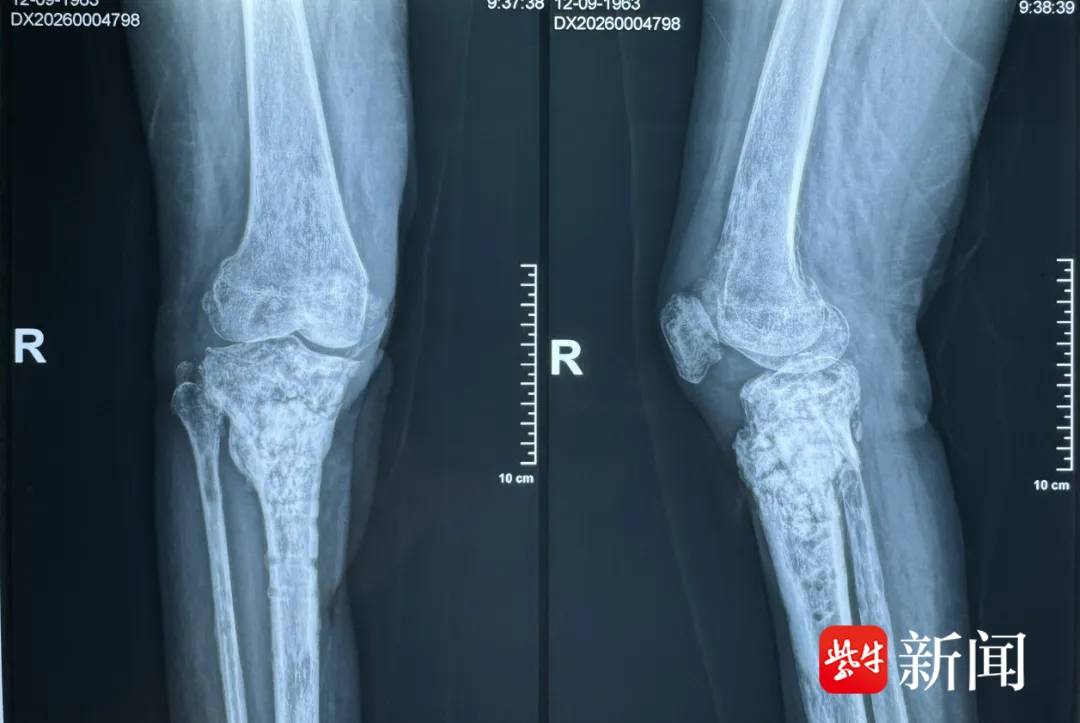

昨日,在连云港市第一人民医院(以下简称连一医)急诊外科的病房里,62岁的李阿姨(化名)终于露出了久违的笑容。自9个月前因右胫骨骨折接受钢板手术后,她的伤口反复渗液、迁延不愈,经历了多次“拆东墙补西墙”的取骨植骨手术,身心俱疲。

9个月前,李阿姨不慎外伤,导致右胫骨骨折,在当地医院接受了钢板内固定手术。谁曾想,这竟是漫长煎熬的开始。术后,她的伤口持续渗液,无法愈合。为了控制感染、填补清创后留下的骨缺损,她不得不辗转多家医院,先后经历了“内固定取出”“皮瓣移植”“抗生素骨水泥填补”等多次手术。

1月12日,因伤口再次持续渗液,李阿姨抱着一线希望来到连一医急诊外科求助。

接诊后,孙晓主任团队对李阿姨的复杂病情进行了详细评估。患者右胫骨慢性骨髓炎明确,且因多次手术,常规从髂骨取骨的路子几乎走不通。怎么办?

首先,在X光透视引导下,通过李阿姨右侧大腿根部一个2cm微创小切口,将特制的RIA系统探入股骨髓腔。系统启动后,钻头在髓腔内缓慢旋转扩髓,同时全程用生理盐水冲洗降温,并通过负压吸引,将扩髓产生的“骨泥”高效收集到专用容器中。